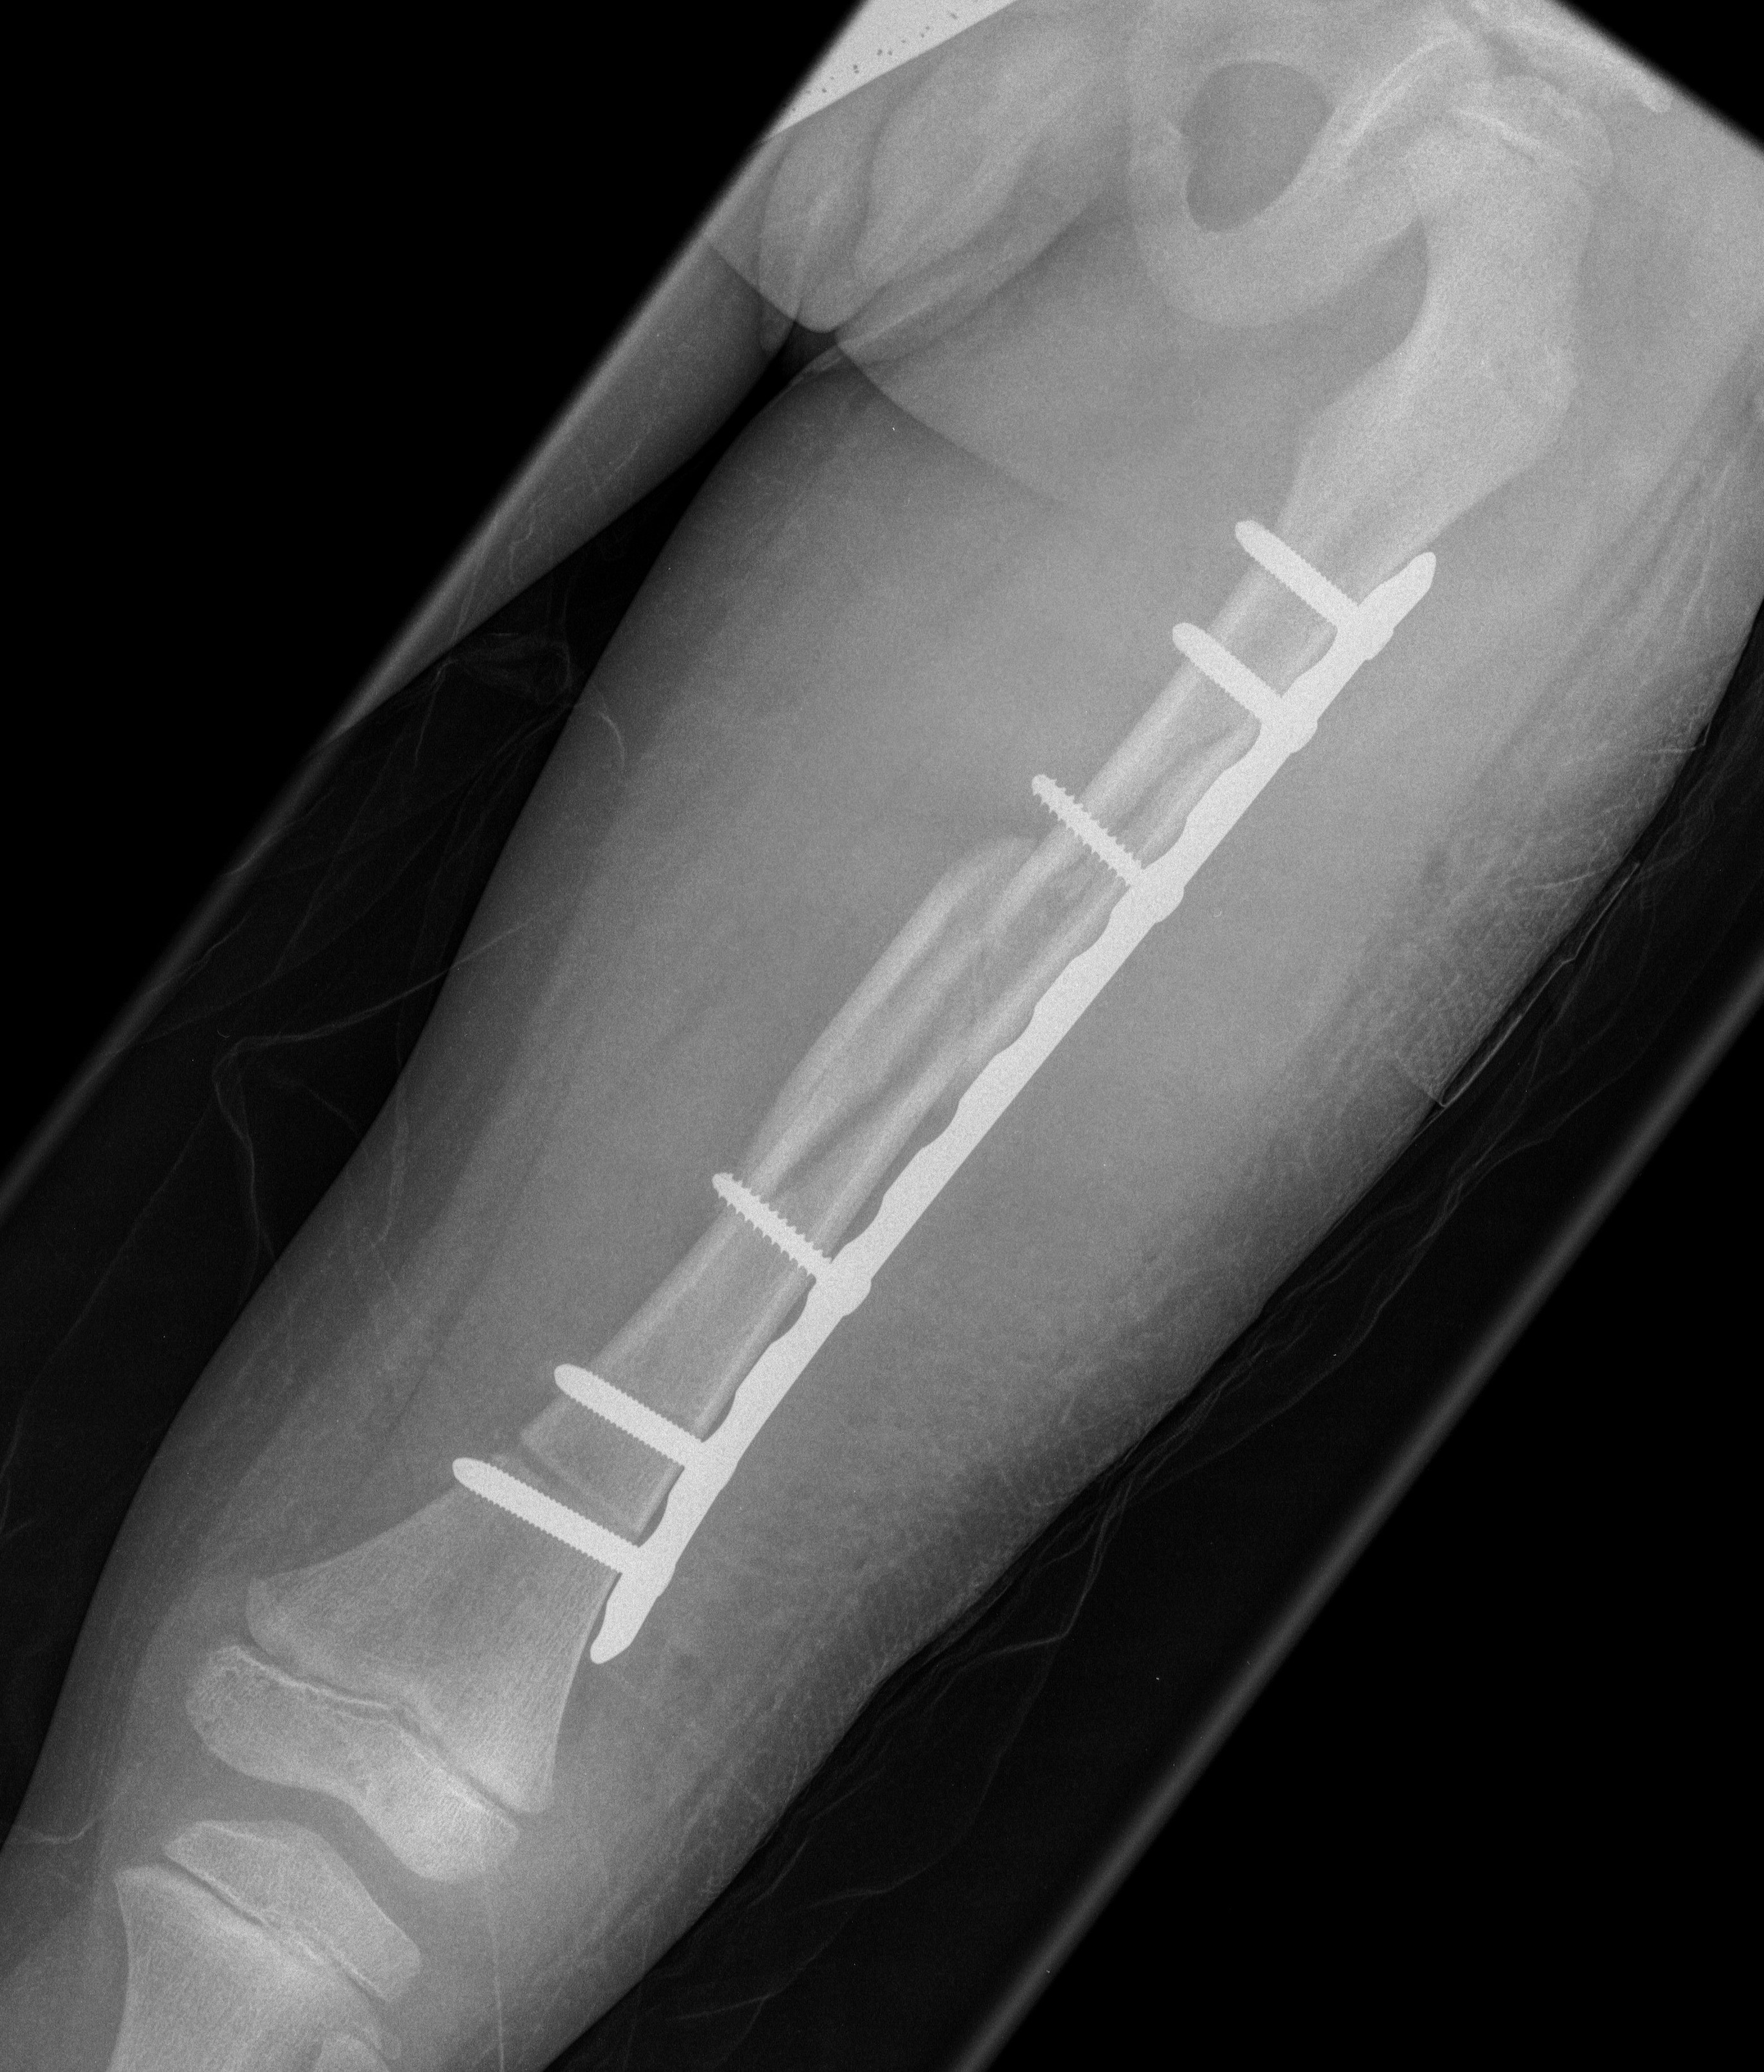

Submuscular bridge plating

POSNA submuscular plating technique video

Technique

- supine on radiolucent table or traction table

- proximal and distal incisions

- blunt dissection to periosteal layer

- run bristow or cobb elevator submuscularly

- 3.5 or 4.5mm LCP plate submuscularly

- indirect reduction techniques

- if inadequate reduction need to open

Abott et al. J Paediatr Orthop 2013

- comparison of open v submuscular bridge plating in 79 patients

- increased blood loss in open plating

- increased rotational asymmetry in bridge plating

- no other difference between two groups